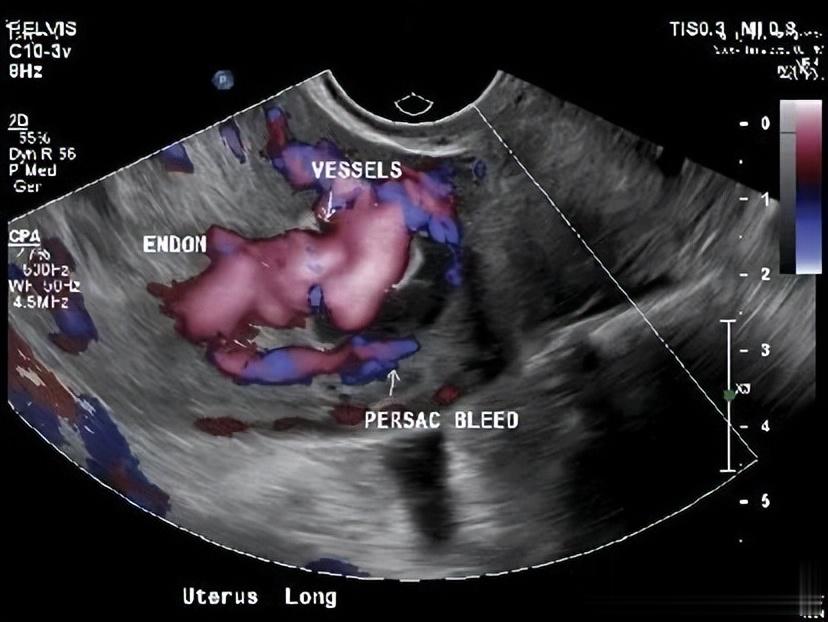

除此以外,超声探及子宫肌层右侧高度血管化区域,怀疑为子宫动静脉畸形,因为血流信号非常丰富,医生们决定必须查清楚。

宫腔镜下,医生看到了一个蓝紫色的血管团,凸向宫腔。

当宫腔压力降低时,它看得不清楚,这也解释了为什么怀孕时能发现,清宫后反而超声显示血流信号不丰富的原因了。

经阴道彩超是首选筛查工具,医生可以看到子宫里有一个富含血流信号的团块,多普勒技术能测到里面血流速度极快、阻力极低的特征,但本案例清宫手术后超声典型特征消失,可造成误诊。

这个案例特别强调了宫腔镜的价值,当超声等影像学检查结果不典型或自相矛盾时,宫腔镜能直接看到那个蓝紫色或暗红色的血管团凸向宫腔,从而一锤定音。